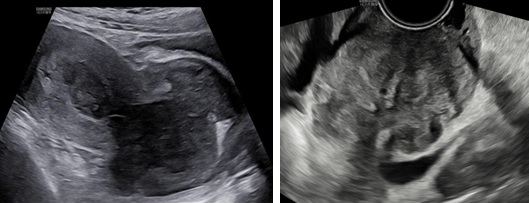

Siêu âm: Tử cung ngã trước, kích thước: 56 x 62 x 90 mm. Cơ tử cung mật độ đều, đồng nhất. Từ thành trước đoạn thân nhô vào lòng tử cung kéo dài tới cổ tử cung có khối echo dày không đồng nhất kích thước 64 x 81 x 70 mm, không rõ ranh giới với cổ tử cung và cơ tử cung. Trên Doppler màu khối tổn thương phần ở lòng tăng sinh mạch máu độ 2 và ở vùng cổ tử cung độ 4.

Kết luận: Theo dõi tổn thương lòng tử cung xâm lấn cổ tử cung

Hình 1: Hình siêu âm 2D ngã bụng (trái) và ngã âm đạo (phải) cho thấy tổn thương từ lòng tử cung lan tới cổ tử cung, không thấy ranh giới của khối này với cơ vùng cổ tử cung